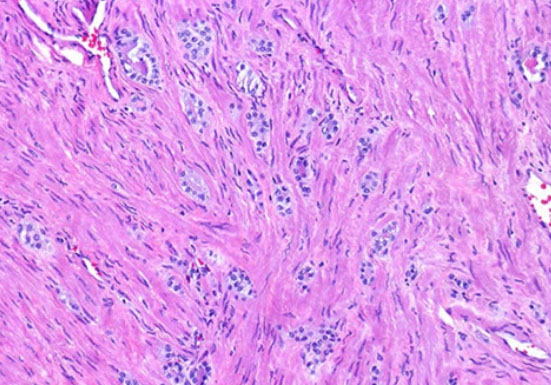

- sclerosing adenosis has mix of well-formed glands, single cells and cellular spindle cell component

To prevent misdiagnosis of malig:

1) AC usually is an extensive process, finding only a small region should lead you to consider sclerosing adenosis or paraganglia

- although sclerosing adenosis is usually well-circumscribed, may be minimally infiltrative at perimeter

2) Glands in sclerosing adenosis resemble those of ordinary adenosis, and are made of cells c pale to clear cytoplasm, and b9-appearing nuclei

- many of the glands have visible basal cells

3) SA has dense spindle cell component not seen in AC, stromal cells plump fusiform cells c amphophilic cytoplasm; stroma has myxoid appearance

- AC usually does not have stromal response or at most a hypocellular fibrotic rxn

4) Has hyaline sheath-like structure around some of the glands

- the glands in AC lack such a collarette and have a "naked" appearance as they infiltrate the stroma

5) the bland cytology of SA helps distinguish from AC, though some glands in SA can be moderately enlarged and have prominent nucleoli

IHC:- S-100 + basal cells

Sclerosing adenosis on needle bx. Note hyaline sheath around some of the glands and individual cells (arrow)